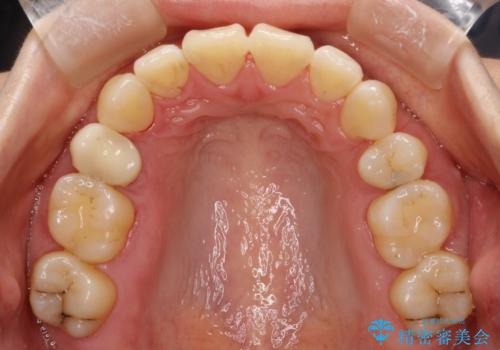

抜歯をして前歯を下げ、ガタつきを取り除く ワイヤー矯正

- 上顎両側第1小臼歯、下顎左側第2小臼歯の3本を抜歯、ラビアルのワイヤー矯正を計画した。